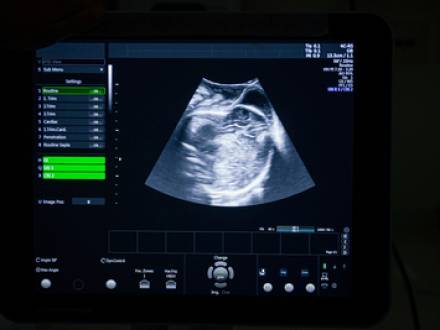

A baby’s position tends to change during pregnancy. Ultrasounds, physical exams, and feeling the mother’s abdomen should help medical professionals determine the baby’s position as it grows. If the fetus does not turn by itself into the proper birth position as the due date nears, your obstetrician should monitor you and the baby closely. He or she should explain the possible treatment options to keep you from experiencing undue complications and injuries.